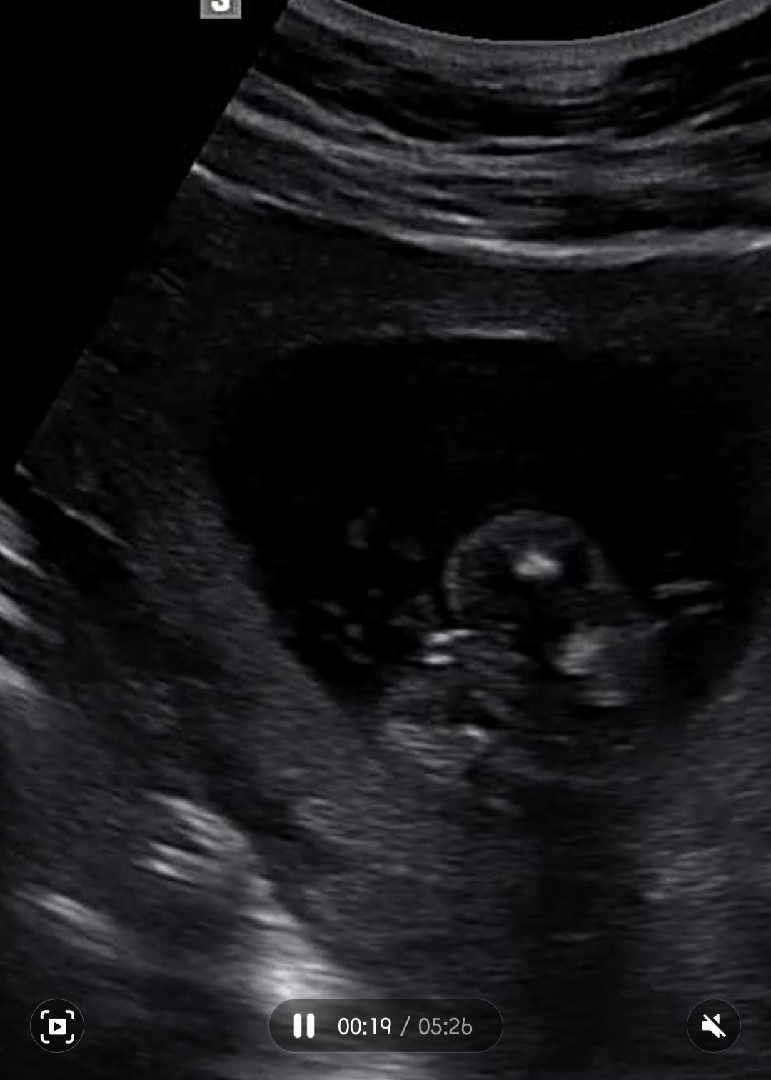

딸이 맞겠죠?

오늘 16주차가 되서 성별 알려주셨어요. 선생님이 12주차에는 모르겠다고 하시더니 오늘은 보자마자 딸이라고 말 안 했냐고 ㅋㅋ 그러면서 삼지창이 보인다고 딸이라고 해주시더라구요. 아들만 있어서 얼떨떨했네요 ㅋㅋㅋㅋ